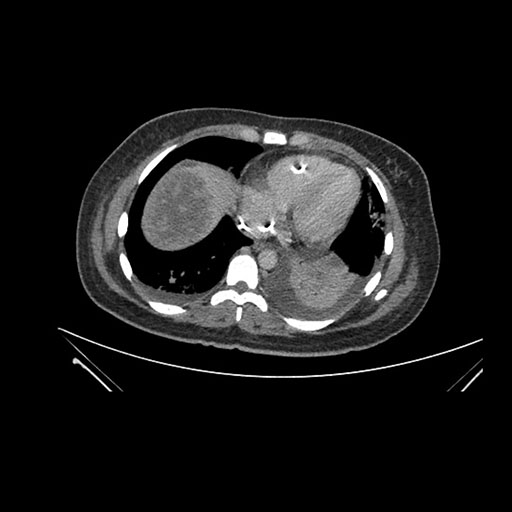

Imaging Analysis

Look through the patient's CT scan to identify any areas of concern for the necessary procedure.

Coronal Venous

Based on initial findings, which issue(s) would you be most concerned about?